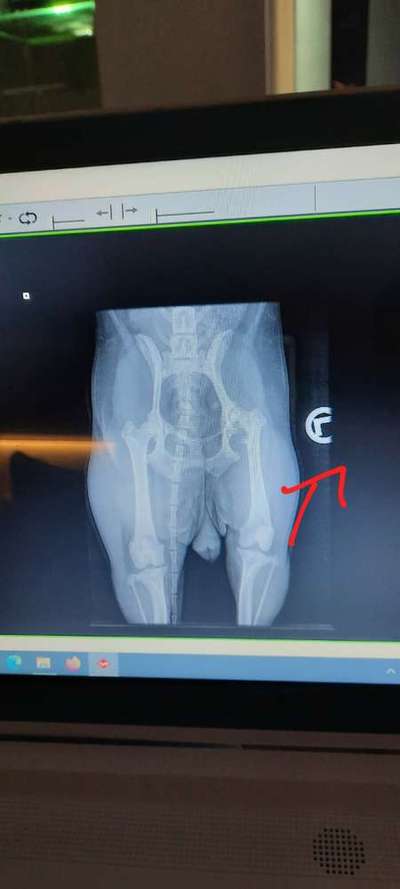

Liebes Team, meine Jack Russel Hündin (6Jahre) hat leider eine kaputte Hüfte hinten Links. Beim Gassi gehen und wenn Sie rennt, entlastet sie immer Ihr Bein und zieht es an. Nach wenigen Sekunden rutscht es wieder in die normale Position. Trotz der kaputten Hüfte rennt, springt und klettert sie als wäre Sie gesund und hätte gar kein Problem mit der Hüfte. Unser Tierarzt und zwei Tierkliniken haben uns empfohlen unbedingt die Hüfte operieren zu lassen. Es liegt laut Arzt eine Patellaluxation und eine Arthrose vor. Die OP sollte eine Femur Kopf Resektion sein. Wir haben große Angst vor dieser Operation und sind uns nicht sicher, ob es wirklich operiert werden muss. Unsere Hündin hat auch panische Angst vor dem Tierarzt immer. Für Sie wäre das sehr viel Stress. Was würden Sie empfehlen? Liebe Grüße Celine